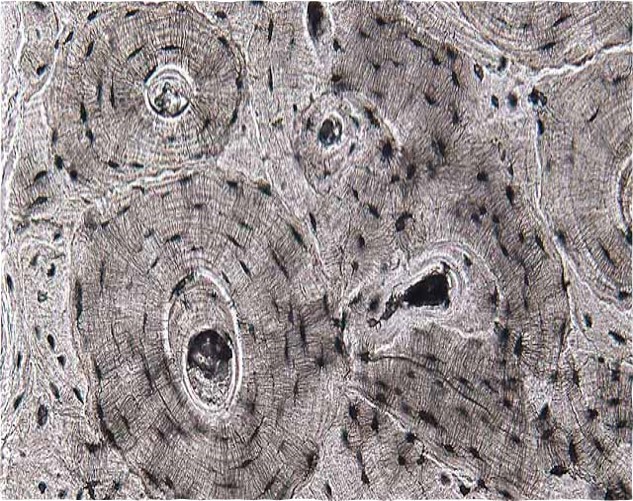

Compact bone